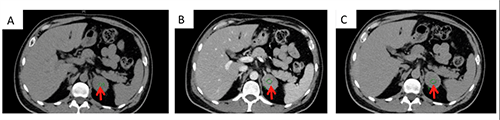

The patient was first diagnosed with an adrenal 4 cm left adrenal mass after a CT scan with contrast was performed following a car accident six months prior to his presentation. A repeat CT with and without contrast confirmed a smoothly marginated but loculated left adrenal gland measuring 40 HU on non-contrast CT (Figure 1A) and an absolute washout of <50 percent (Figure 1B-C).

Figure 1. Computed tomography of abdomen confirming a 4 x 4 cm left adrenal mass on axial view. A: Precontrast view, 40 HU; B: Postconstrast view, 83 HU; C: Washout seen with 15 minute delayed view with contrast, 52 HU